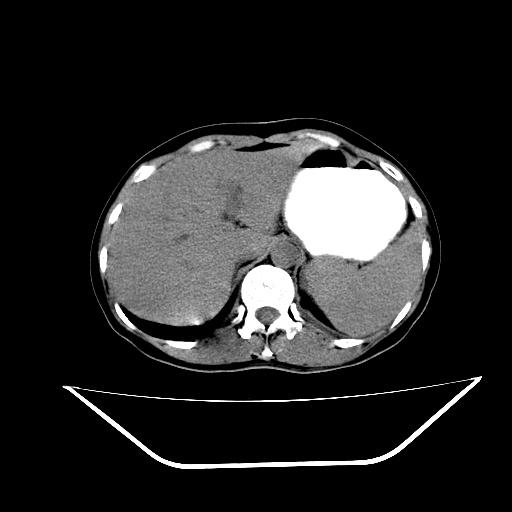

胰头占位ct讨论

胰头占位?(ct讨论)

红圈内为胰头占位病变,蓝圈内为胆总管.